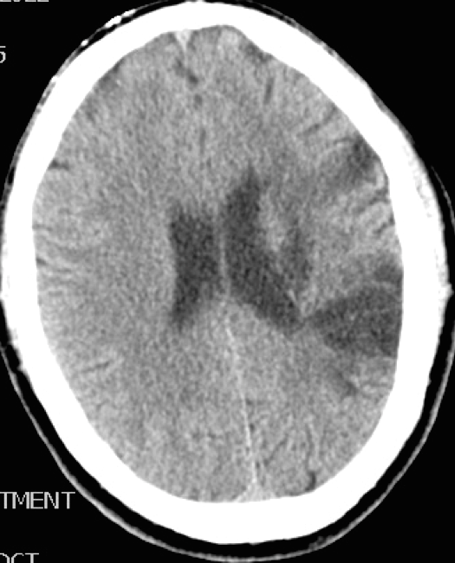

What is the difference between a Cortical and a subcortical infarct?

Both will present with contrallateral weakness and numbness

Cortical infarct will have aphasia alsp

subcortical will not have aphasia